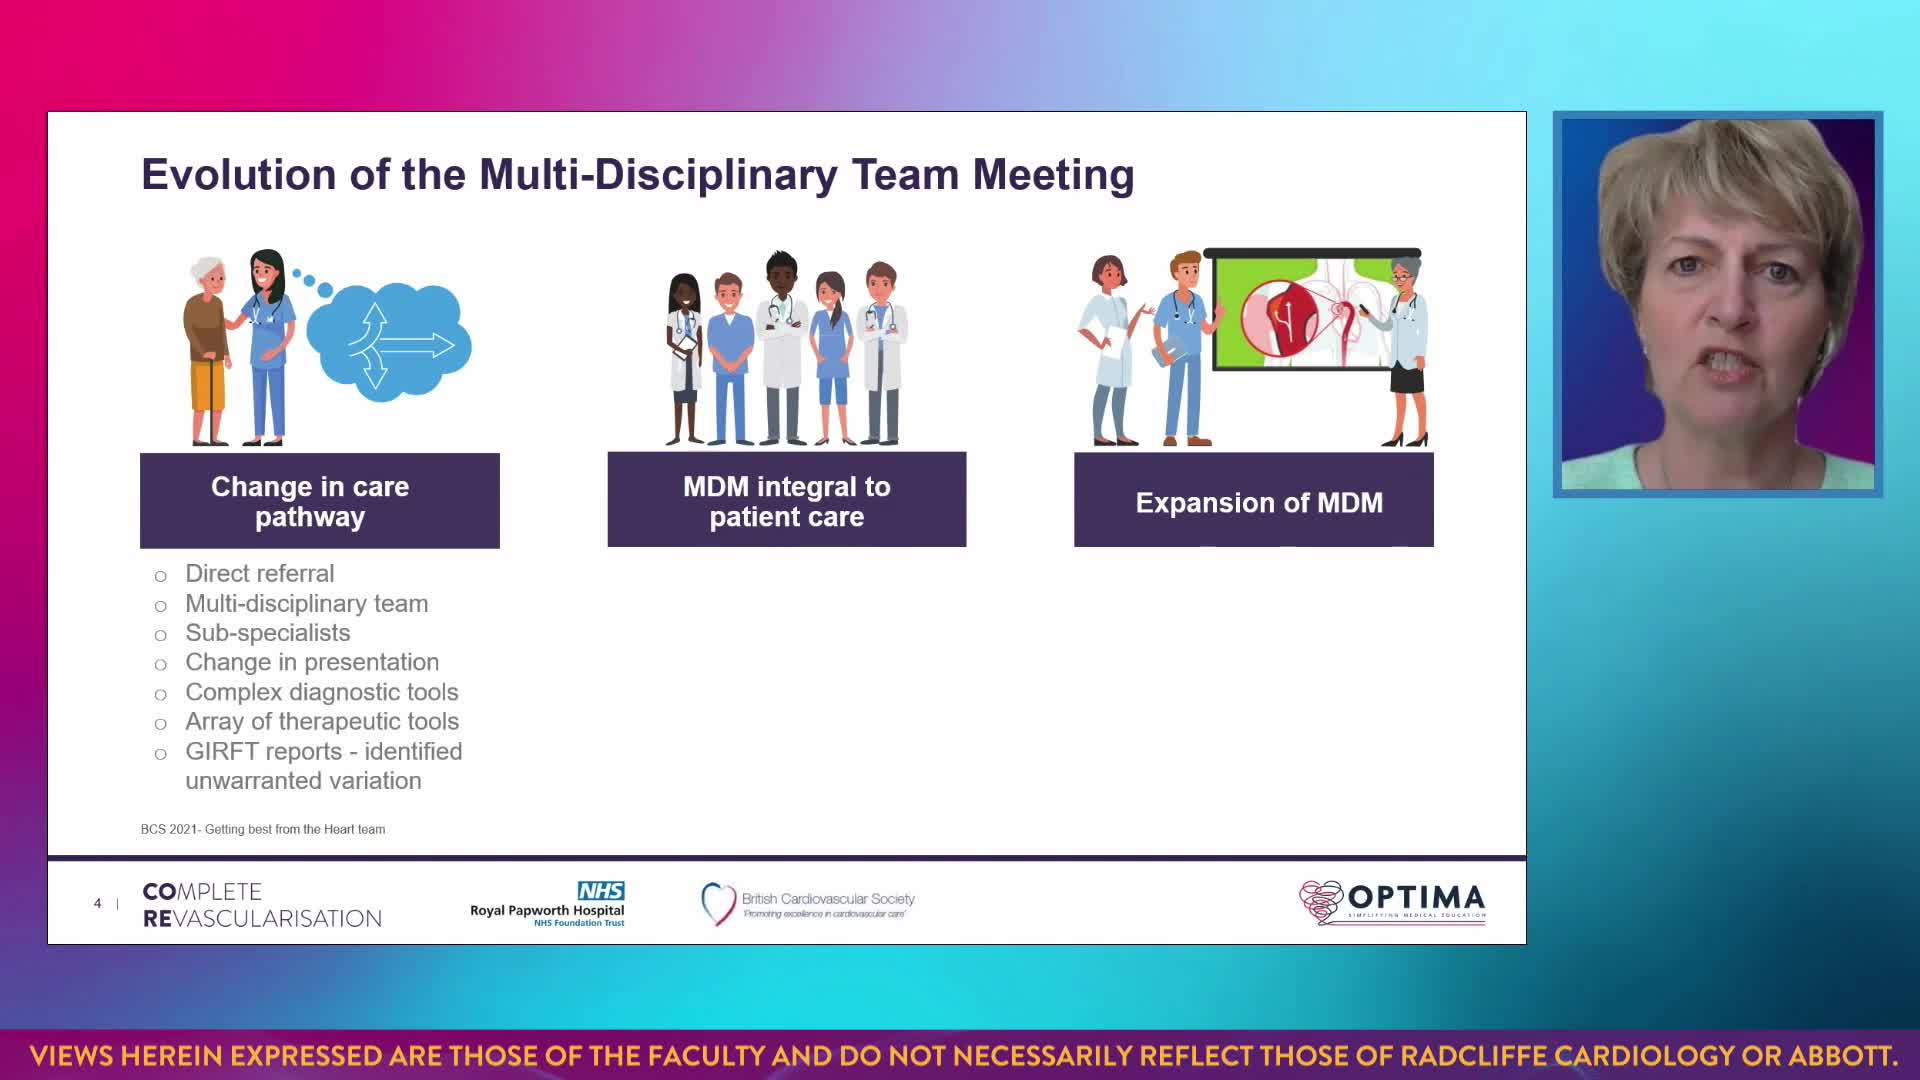

Session 1: Pre-procedure planning – are we lost without a map?